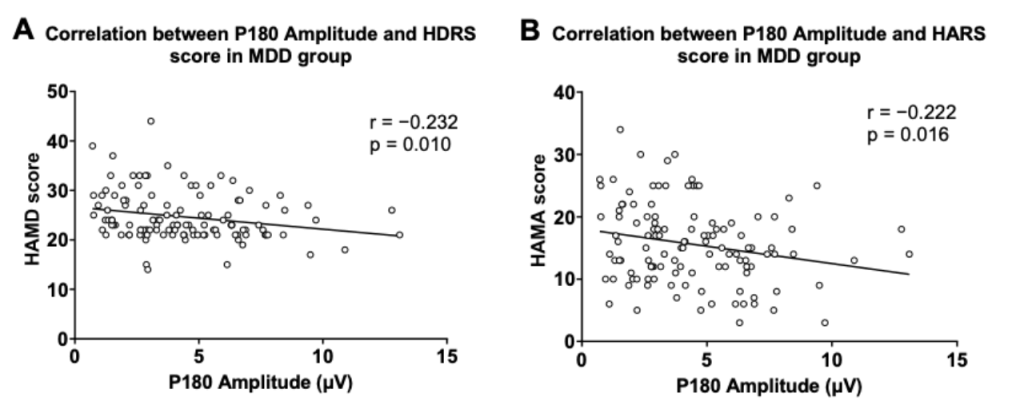

圖2. P180波幅與抑郁及焦慮癥狀得分的關系

圖1分別顯示了健康對照組與患者組的TMS誘發腦電的蝴蝶圖。研究結果顯示,抑郁癥患者P180波幅顯著低于健康對照人群。在抑郁癥患者中,P180波幅與抑郁、焦慮癥狀得分呈顯著負相關;P30波幅與RBANS視覺空間/結構得分和總分呈顯著負相關。

多元回歸分析表明,P180波幅能負向預測患者的抑郁及焦慮癥狀;P30波幅、發病年齡和教育程度能負向預測患者的認知功能。